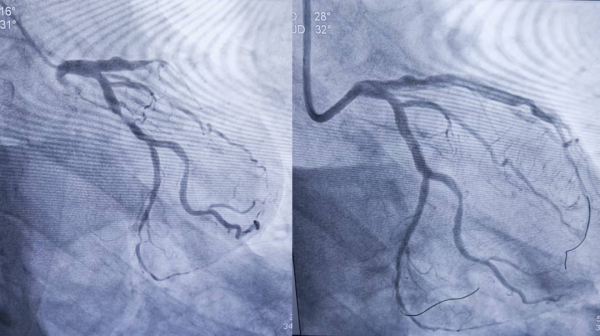

1、39歲男性,前降支閉塞,行血栓抽吸+冠脈內溶栓。

2、71歲男性,右冠閉塞,行藥物球囊擴張成形術。

3、69歲男性,雙支病變,行介入治療。